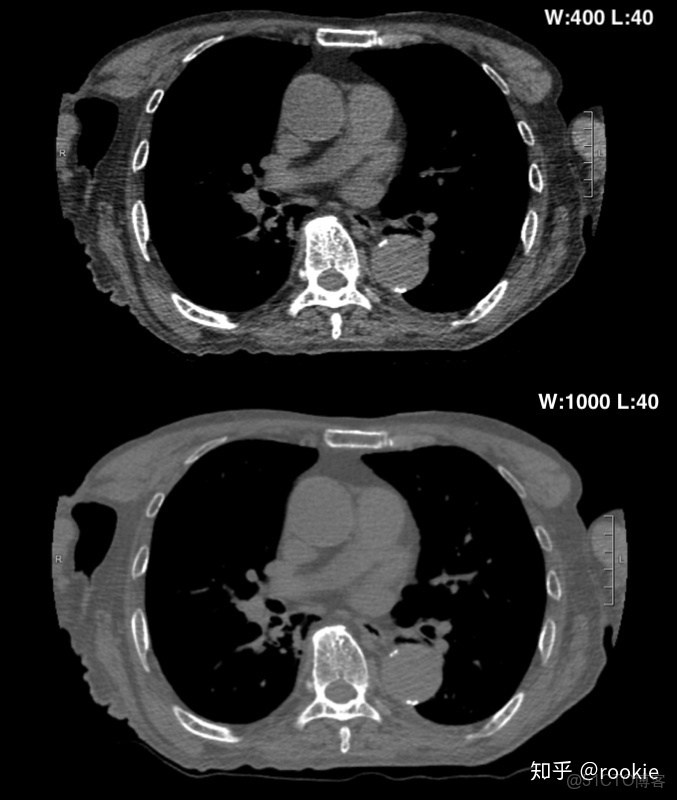

上面的圖像顯示了增加窗口寬度將如何降低圖像的對比度。與下窗格相比,頂部窗格的窗口寬度更小,皮下組織中的肌肉和脂肪之間的對比更加明顯。